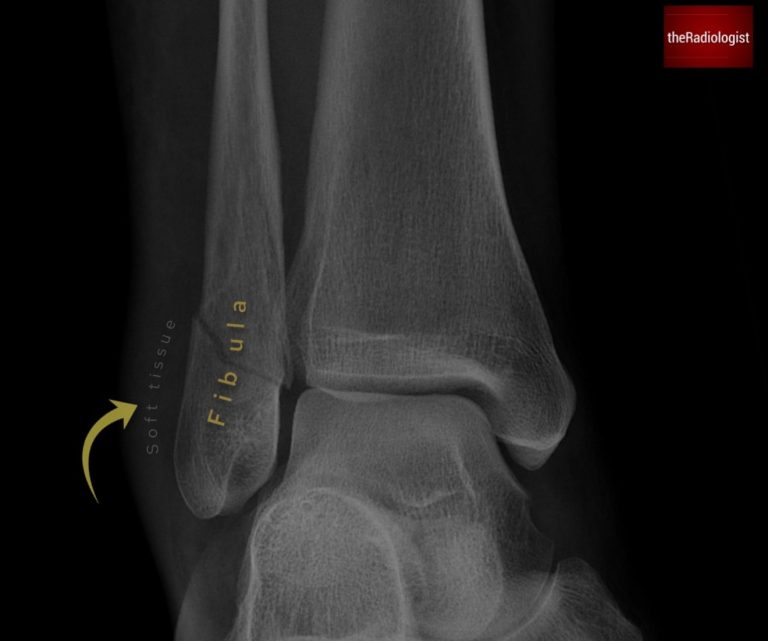

Always start with the soft tissues. Swelling, asymmetry, or gas locules can point you to the site of injury before you even find a fracture. For example, swelling over the lateral malleolus is a clue to a distal fibula fracture.

Swelling of the soft tissues overlying the lateral malleolus leads us to a distal fibula fracture which may not always be as obvious as this one.